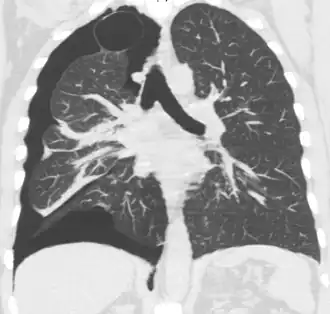

Computed tomography

A CT scan is not necessary for the diagnosis of pneumothorax, but it can be useful in particular situations. In some lung diseases, especially emphysema, it is possible for abnormal lung areas such as bullae (large air-filled sacs) to have the same appearance as a pneumothorax on chest X-ray, and it may not be safe to apply any treatment before the distinction is made and before the exact location and size of the pneumothorax is determined.[18] In trauma, where it may not be possible to perform an upright film, chest radiography may miss up to a third of pneumothoraces, while CT remains very sensitive.[21]

A further use of CT is in the identification of underlying lung lesions. In presumed primary pneumothorax, it may help to identify blebs or cystic lesions (in anticipation of treatment, see below), and in secondary pneumothorax, it can help to identify most of the causes listed above.[18][22]